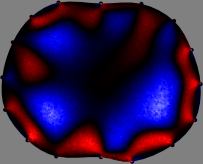

Figs. 3 and 4 compare the performance of the proposed FER method in (20) with the standard regularized least-squares method ((19) when is the identity matrix). The regularization parameter of the standard method was heuristically chosen for its best performance, and the parameter of the FER method was set to be one of three different values . The injection current was 1 mA at 100 kHz, and the frame rate was 9 frames per second. The reference frame at was obtained from the maximum expiration state. The measured data, , represent the voltage differences between each time and . The blue regions, which denote where conductivity decreased by inhaled air, increased during inspiration and decreased during expiration. The FER method with was clearly more robust than the standard method that produced more artifacts originated from the inversion process.

| Standard | |

||||||||||

| FER () | |

| FER () | |||||||||||